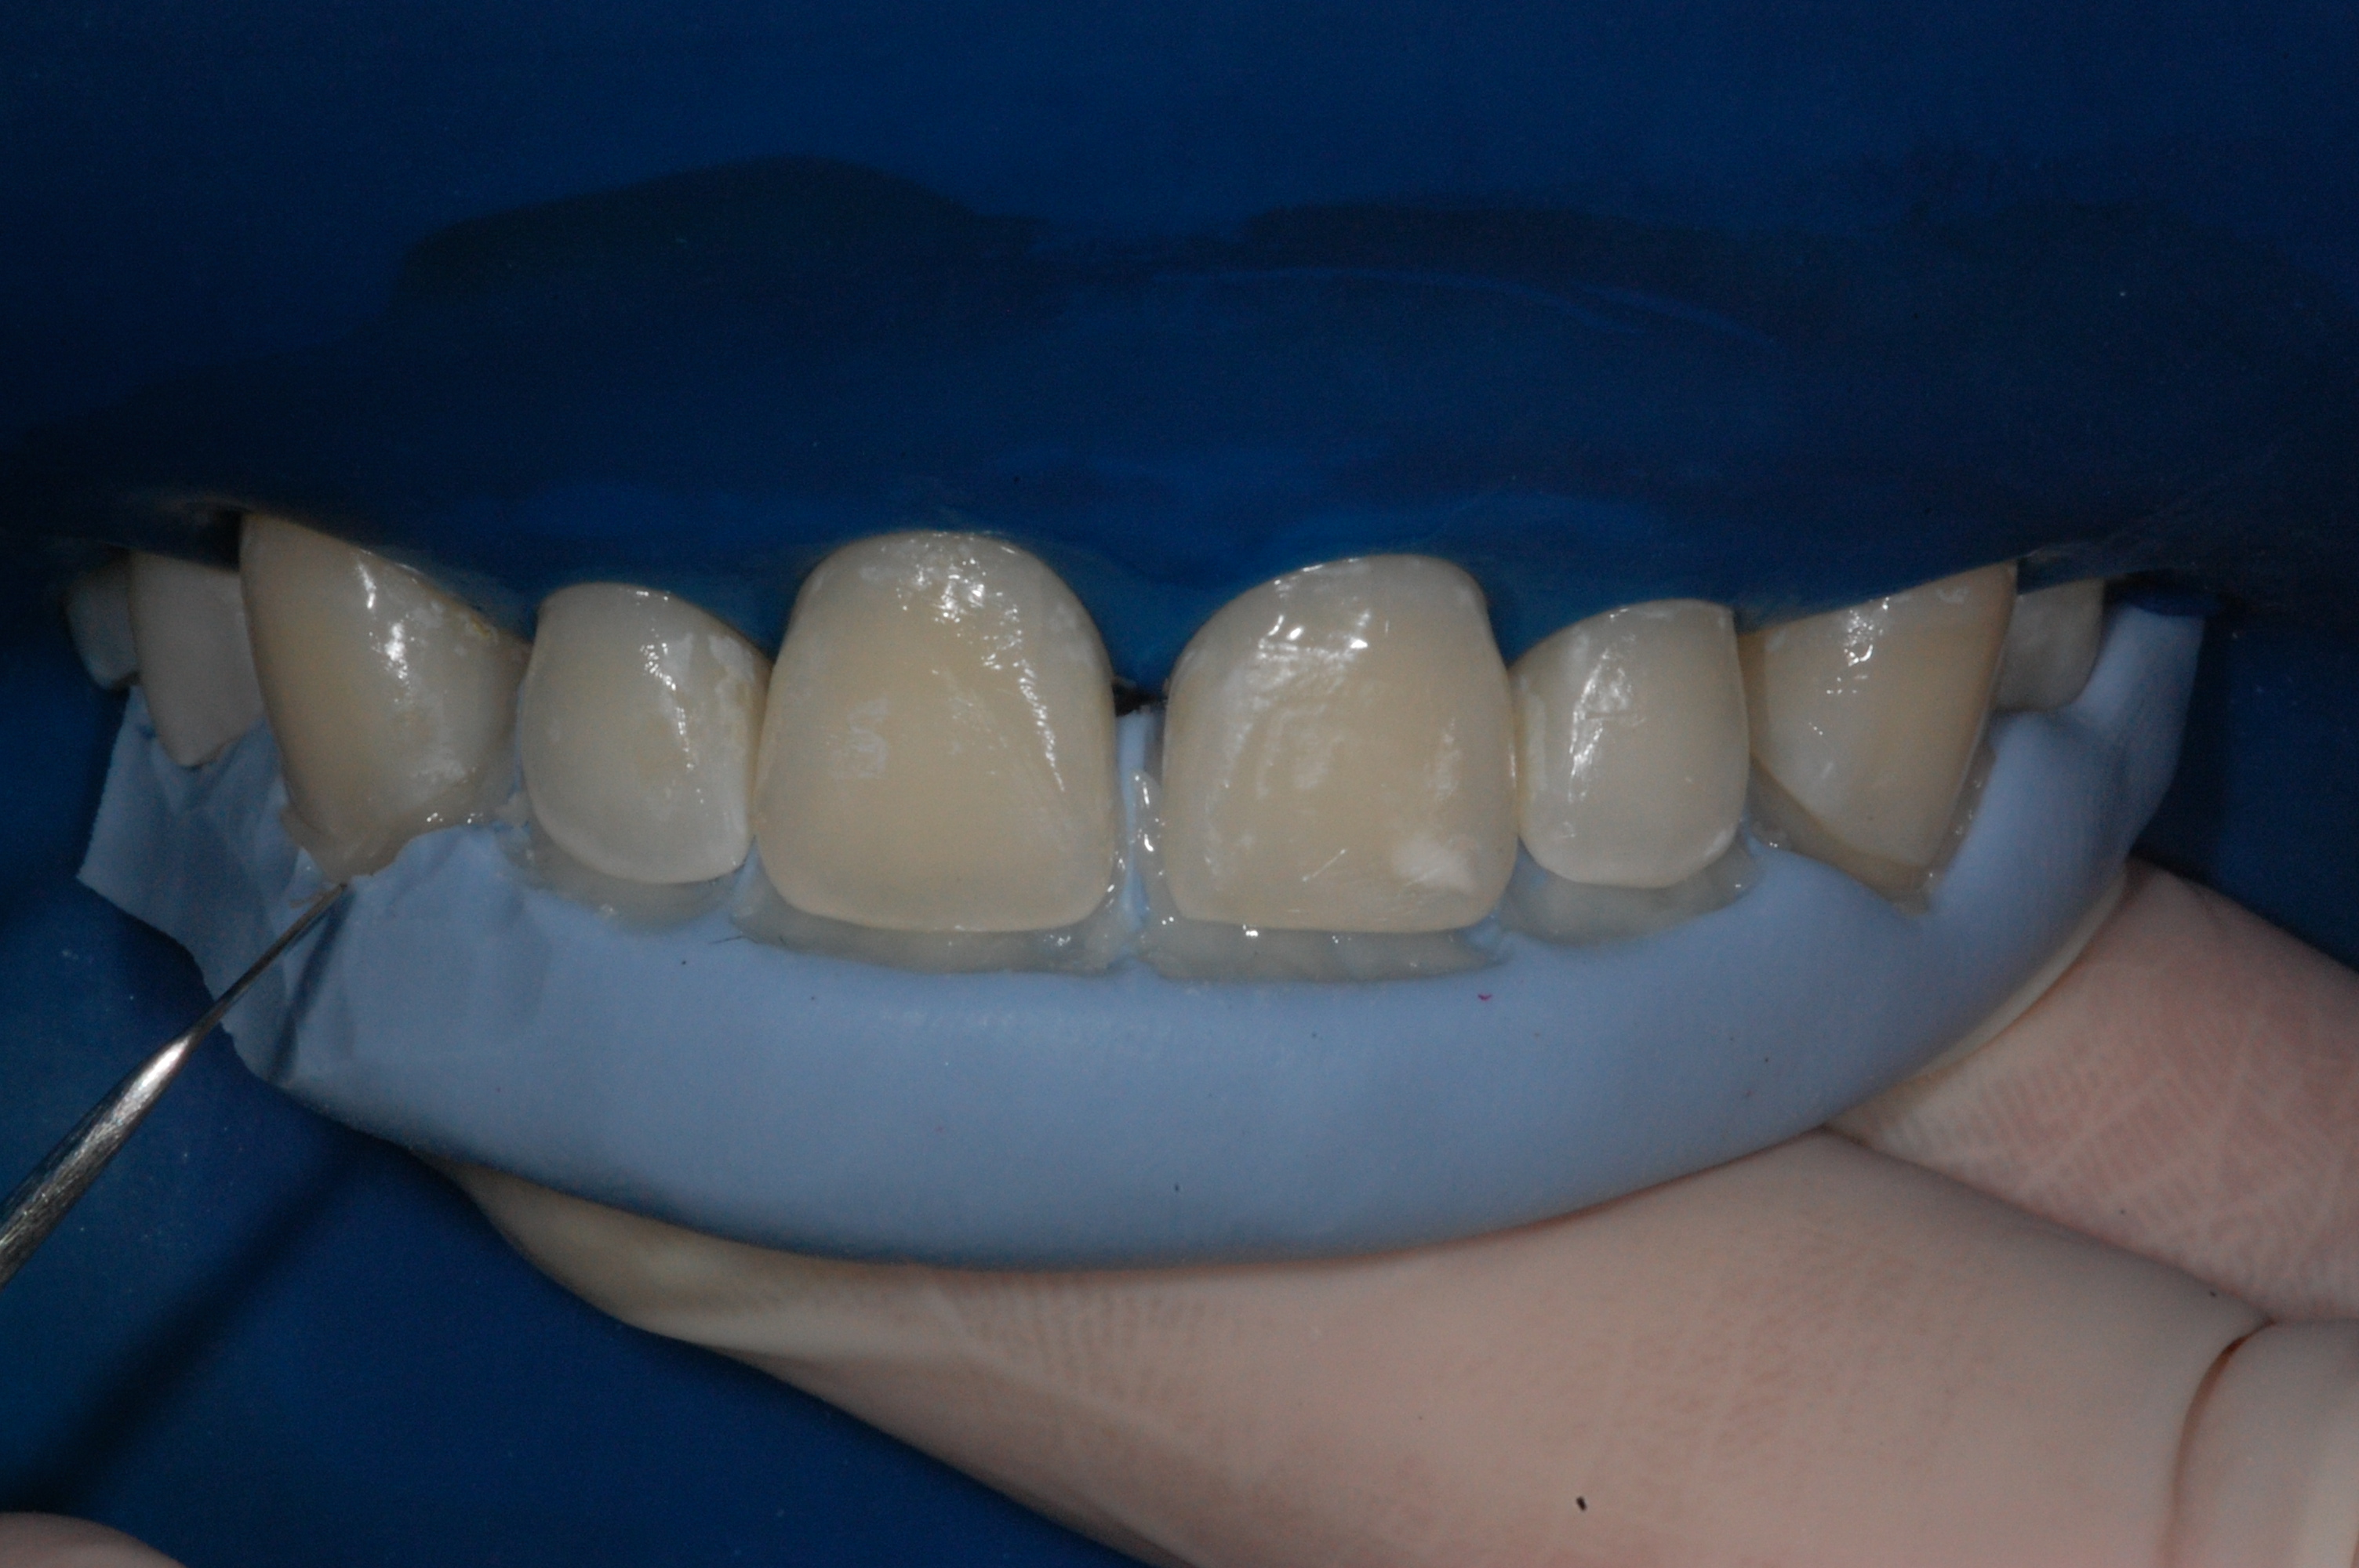

The presence of diastema, between anterior teeth, distorts a pleasing smile by concentrating the observer’s attention on the spaces. The patient’s needs and expectations must be considered in the process of treatment planning to ensure satisfaction with the treatment outcomes. There are many forms of therapy that can be used for diastema closure. A carefully developed diagnosis, which includes a determination of the causal elements and advanced treatment planning, allows the most appropriate treatment to be selected for each case. The aim of this paper is present a multidisciplinary approach as a solution to multiple diastemas in the anterior region using gingival tissue recontouring and direct adhesive restorations, with minimum wear of the dental structure, after the orthodontic intervention discussing the minimal intervention to obtain imperceptive and aesthetic final restoration. Thirty-six months after the treatment was carried out, the final aesthetic was maintained with all dental element details and gingival tissue harmony, without recurrence of periodontal pockets and the preservation of the tooth color and shape.